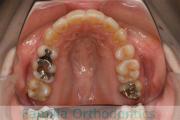

No.23V-061

- 主な症状:

- 叢生

- その他の症状:

- 上下顎前突

- 年齢:

- 23歳

- 性別:

- 女性

- 抜歯部位

- 上:

- 44

- 下:

- 主な使用装置:

- FEA 022

- 治療にかかった費用:

- 88万円

でこぼこを綺麗に並べたいということで来院されました。上下左右から小臼歯を抜歯して、マルチブラケット法を2年半、30回程度通院していただいて行いました。

かなり強い叢生(でこぼこ、凹凸、ガタガタ)のため、保定をしっかりしないと後戻りのリスクが高いケースといえます。

- ≫治療前

-

上顎

下顎

前歯の関係など